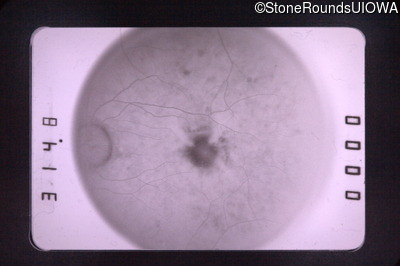

Fluorescein Angiography - Left - 20/400

Exemplar